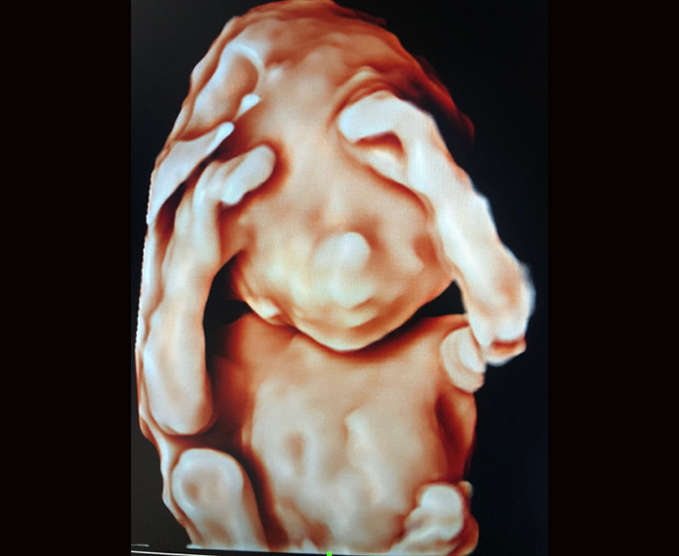

El ultrasonido obstétrico utiliza ondas sonoras para producir imágenes de un bebé (embrión o feto) que está dentro de una mujer embarazada, como así también del útero y los ovarios de la madre. No utiliza radiación ionizante, no tiene efectos nocivos conocidos, y es el método preferido para la vigilancia de las mujeres embarazadas y sus bebés que aún no han nacido.

Además utilizamos los mejores equipos. Agenda tu cita hoy mismo